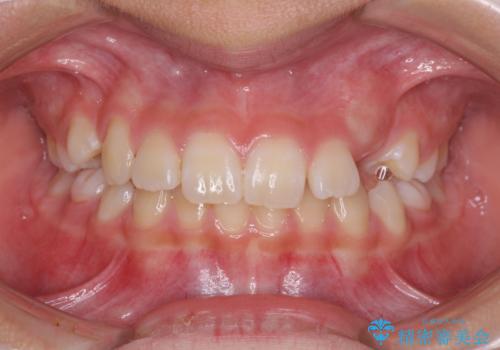

- 小学校での定期歯科検診にて歯列不正を指摘されたとのことで来院された患者様です。

左上の犬歯が低位に埋伏しており、将来八重歯になるリスクが高いと判断されたため、補助装置とワイヤーを用いて犬歯を通常の位置まで移動させることとしました。